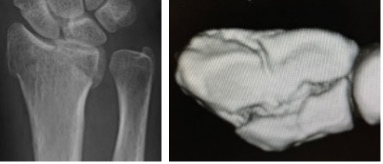

橈骨遠位端骨折に対する鏡視併用手術

橈骨遠位端骨折は頻度の高い骨折の一つで、特に関節内骨折については関節鏡を併用し従来のX線のみでは整復が不十分な関節面の整復を行っています。

術前

術後

鏡視下整復前

整復後